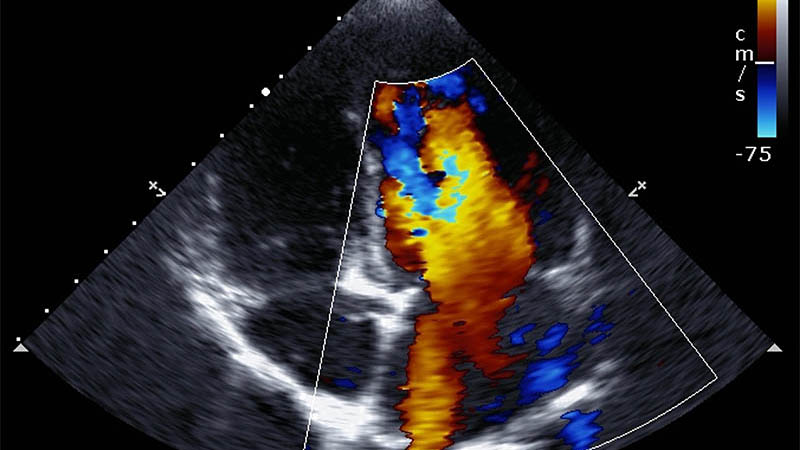

Ultrasound

Ultrasound (sonography) is a medical imaging test that uses high-frequency sound waves to create real-time pictures of organs and tissues inside the body. Unlike X-rays, CT, or PET scans, ultrasound does not use radiation.

Uses high-frequency sound waves to create images of internal organs and tissues.

- Non-invasive and does not use radiation

- Used to evaluate tumors in the abdomen, pelvis, and breast

- Can guide biopsies